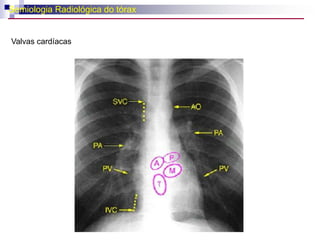

Semiologia Radiológica do tóraxRadiologia Cardiovascular - Anatomia

Semiologia Radiológica dotóraxRadiologia Cardiovascular - Anatomia

CorazónLas válvulas son:1) Derecha: válvula tricúspide. Tiene tres valvas cúspides: superior, inferior e interna.2) Izquierda: válvula mitral. Tiene dos valvas.

CorazónLas válvulas son:1)Derecha: válvula tricúspide. Tiene tres valvas cúspides: superior, inferior e interna.2) Izquierda: válvula mitral. Tiene dos valvas.